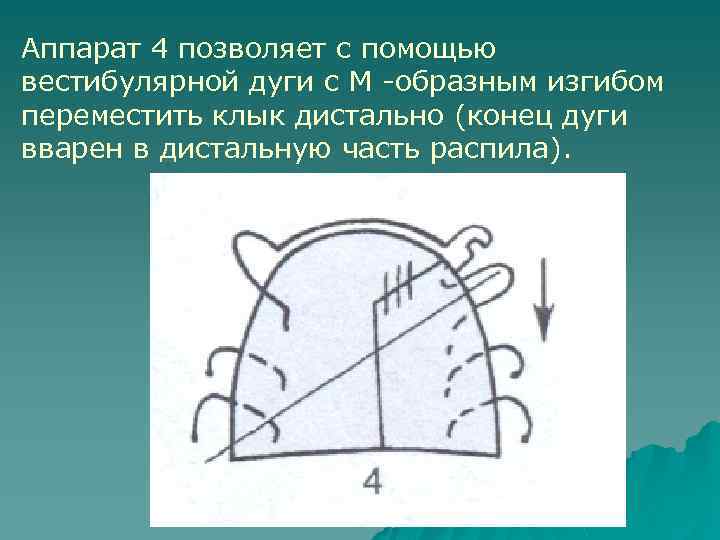

Аппарат 4 позволяет с помощью вестибулярной дуги с М -образным изгибом переместить клык дистально (конец дуги вварен в дистальную часть распила).